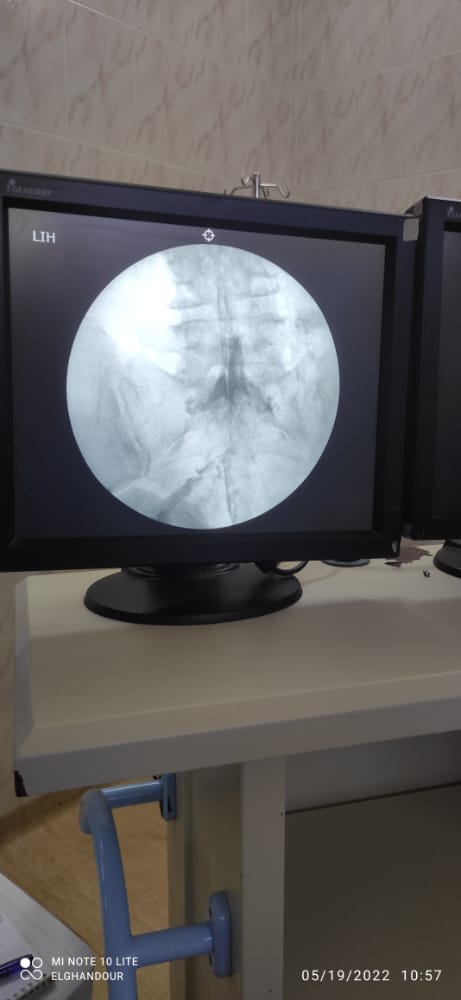

قام الفريق الطبي بوحدة علاج الألم بمستشفي الزقازيق العام، بقيادة الدكتور وائل أحمد الحبشاوي استشاري علاج الألم والتخدير، والدكتور يحيى الغندور أخصائي علاج الألم والتخدير، بعلاج حالتين وتقديم الخدمات الطبية لهما بالوحدة، بدون أي تدخل جراحي، حيث تم استقبال السيدة الأولي والتي تبلغ من العمر ٥٨ عام، وكانت تعاني من آلام بالرقبة وخدر وتنميل بالطرف العلوي الأيسر، وآلام أسفل الظهر وعرق النسا بالساق اليمنى، والتهاب بمفاصل العمود الفقري، بسبب غضاريف معتلة متعددة المستويات بالفقرات القطنية والعجزية، مع رفضها للتدخل الجراحي، وتم عمل حقن فوق الأم الجافية لجذور الأعصاب والقناة العصبية بالرقبة والفقرات القطنية والعجزية بمواد مضادة للإلتهاب، وتم عمل تسليك للقناة العصبية بمواد مذيبة للإلتصاقات، كما تم حقن مفصل الحوض الحرقفي المعتل، وعمل تردد حراري نابض على جذور الأعصاب، وعمل كي بالتردد الحراري على الأعصاب الناقلة للألم من المفاصل الخلفية للفقرات القطنية والعجزية، وتم خروج المريضة وتحسن الحالة بالمتابعة في العيادة، مع توجيهها لإجراء جلسات العلاج الطبيعي، وكانت الحالة الثانية مريض يبلغ من العمر ٥٥ عاما، يعاني من آلم أسفل الظهر وألم بالساقين نتيجة لضيق القناة العصبية بمنطقة الفقرات القطنية، وتم حقن القناة العصبية بمواد مذيبة للإلتصاقات مع مواد مضادة للإلتهابات، وتم خروج المريض بحالة جيدة بعد تقديم العلاج اللازم له، مع التوصيات الطبية بالمتابعة بعيادة علاج الألم.